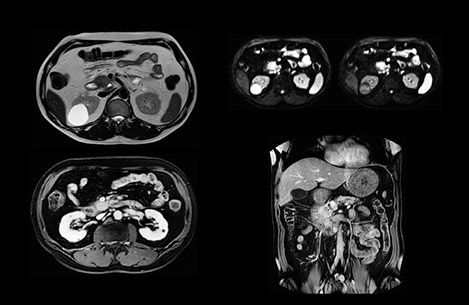

In this example the image quality of the MultiVane XD images is evidently better than in the images without MultiVane XD. Ingenia 1.5T with dS Torso coil solution.

Dr. Baumann then implemented MultiVane XD for motion correction. It uses an extended reconstruction algorithm for imaging that is virtually motion free. “With MultiVane XD we get excellent motion-corrected images with high spatial resolution. We typically first optimize our scan for high image quality, and when satisfied with that, we try to reduce the scan time. So, we combined MultiVane XD with dS SENSE, which allows us to shorten the scan time,” he explains. “The performance of MultiVane XD in liver imaging is outstanding. MultiVane XD with dS SENSE is a powerful development in improving liver image quality.” “As we use breathhold imaging for T2-weighted liver scans, we depend on the patient’s ability to cooperate with the exam. This can present a real challenge when we are looking for small lesions, such as in our oncological patients. However, with MultiVane XD motion correction, we get excellent images. This is important for our surgeons, because they want to know exactly where the lesions are.”

“Our liver exams are quite fast,” says Dr. Baumann. “If the patient tolerates it, we use an arms-up position to reduce the FOV and speed up the exam with dS SENSE.” “We acquire one transversal high resolution T2-weighted sequence with 3 mm slice thickness, for example for pancreas or liver lesions. Then we also add a T2 fat suppressed MultiVane XD SPIR sequence. We perform these two routinely in our liver imaging. We use high dS SENSE factors to significantly shorten scan times to 2-4 minutes, which can improve our protocol; it’s a very robust scan.” “We include mDIXON for the dynamic sequences because of the robust and homogeneous fat suppression we get with that. We had been using eTHRIVE, but we are now quite happy with mDIXON. Sometimes we use a medication to calm the bowels, to further improve the image quality.”